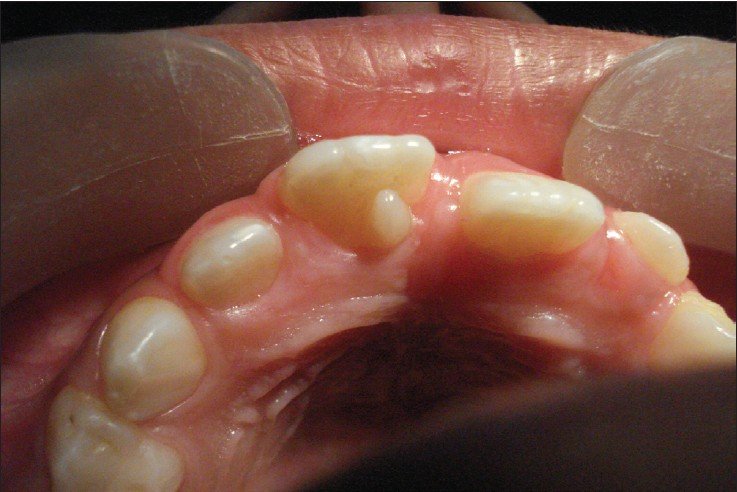

Talon cusp

Source- textbook of oral pathology Shafers and Google images